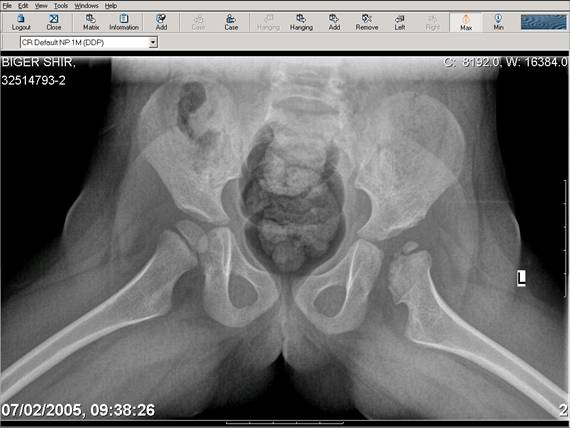

Chto by ne byt goloslovnym posilau vam svoi sluchai gde sdelal vse chto napisal vyshe